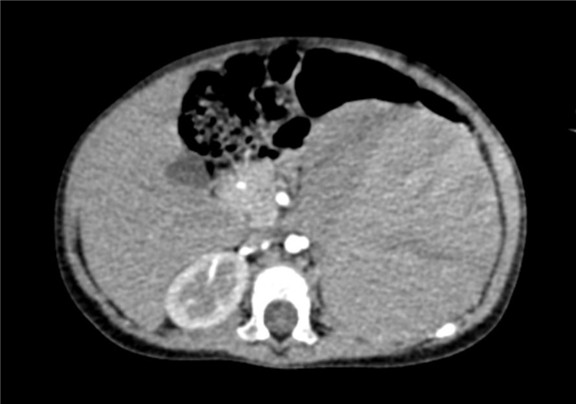

2017-02-03 上腹部CT平扫:左肾区巨大占位,肾母细胞瘤?建议CT增强检查;右肾结石可能性大;腹腔积液。

将0.625mm双源薄层CT资料的静脉期和动脉期Dicom格式文件导入海信CAS系统。

通过调节窗宽窗位调整CT序号,对肿瘤,肝实质,胆囊,下腔静脉,肿瘤,肝动脉、门静脉及肝静脉等进行三维重建;系统自动计算肿瘤体积和肝脏体积。

模拟手术操作,自动计算切除肿瘤体积。肝脏体积为496.9ml,肾上腺肿瘤体积363ml,术前规划手术方案,进行手术。

术前CT检查:

动脉期

静脉期